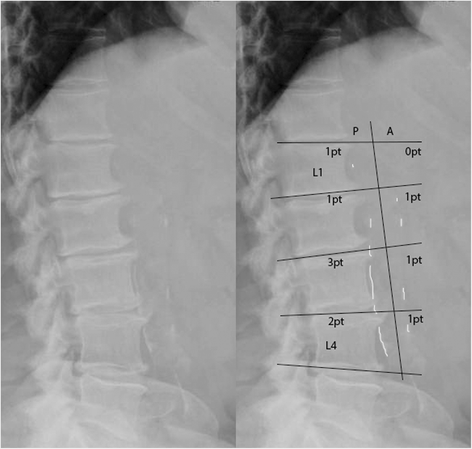

Calcium chloride CaCl2 injury model was used to create local arterial calcification abdominal aortic region in rats. 10 male Sprague-Dawley SD rats 56 weeks old were placed under general anesthesia 2 to 3 isoflurane and the infrarenal abdominal aorta was exposed and treated periadventitially with 020 molL CaCl2by placing CaCl2-soaked sterile cotton gauze on the aorta for. Since the AAC can be quantified easily using a lateral lumbar X-ray we hypothesized that the extent of AAC as assessed on a lateral lumbar X-ray might be predictive of the presence of significant CAD in dialysis patients.

In recent years there has been a growing concern that abdominal aortic calcification AAC has a predictive effect on the prognosis of patients with end-stage renal disease ESRD. Treatment is to lower cholesterol diet exercis. 6 Autopsy studies of 600 middle-aged adults in the 1950s reported highly significant positive associations between the degree of abdominal aortic calcification and the presence of calcified plaque in the coronary arteries.